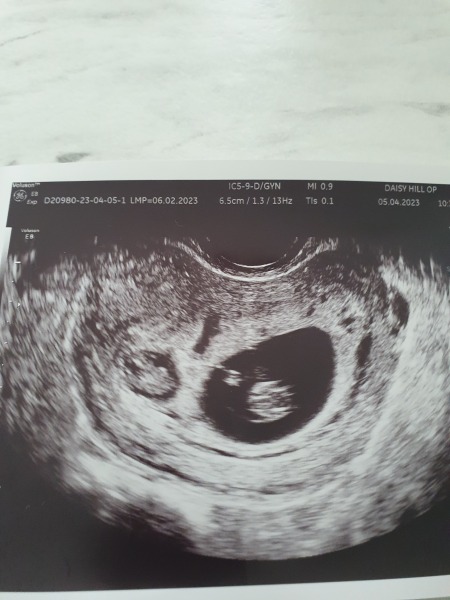

Hi all, just found out at week 8 week scan today that there's a second little baby

Baby A is measuring 8w+2, heartbeat strong at 169 and all looking great, so pleased

Baby B is in a tiny gestational sac, measuring 7w+4 and amazingly also had a good strong heartbeat 150

The doctor doesn't seem too confident that Baby b will progress given the tiny gest sac and measuring behind, I was shocked to see even a heartbeat when I saw how small it looked, i was surprised it even measured 7w+4. the baby looks OK i think but the gest sac is way too small, it's crowded in there.